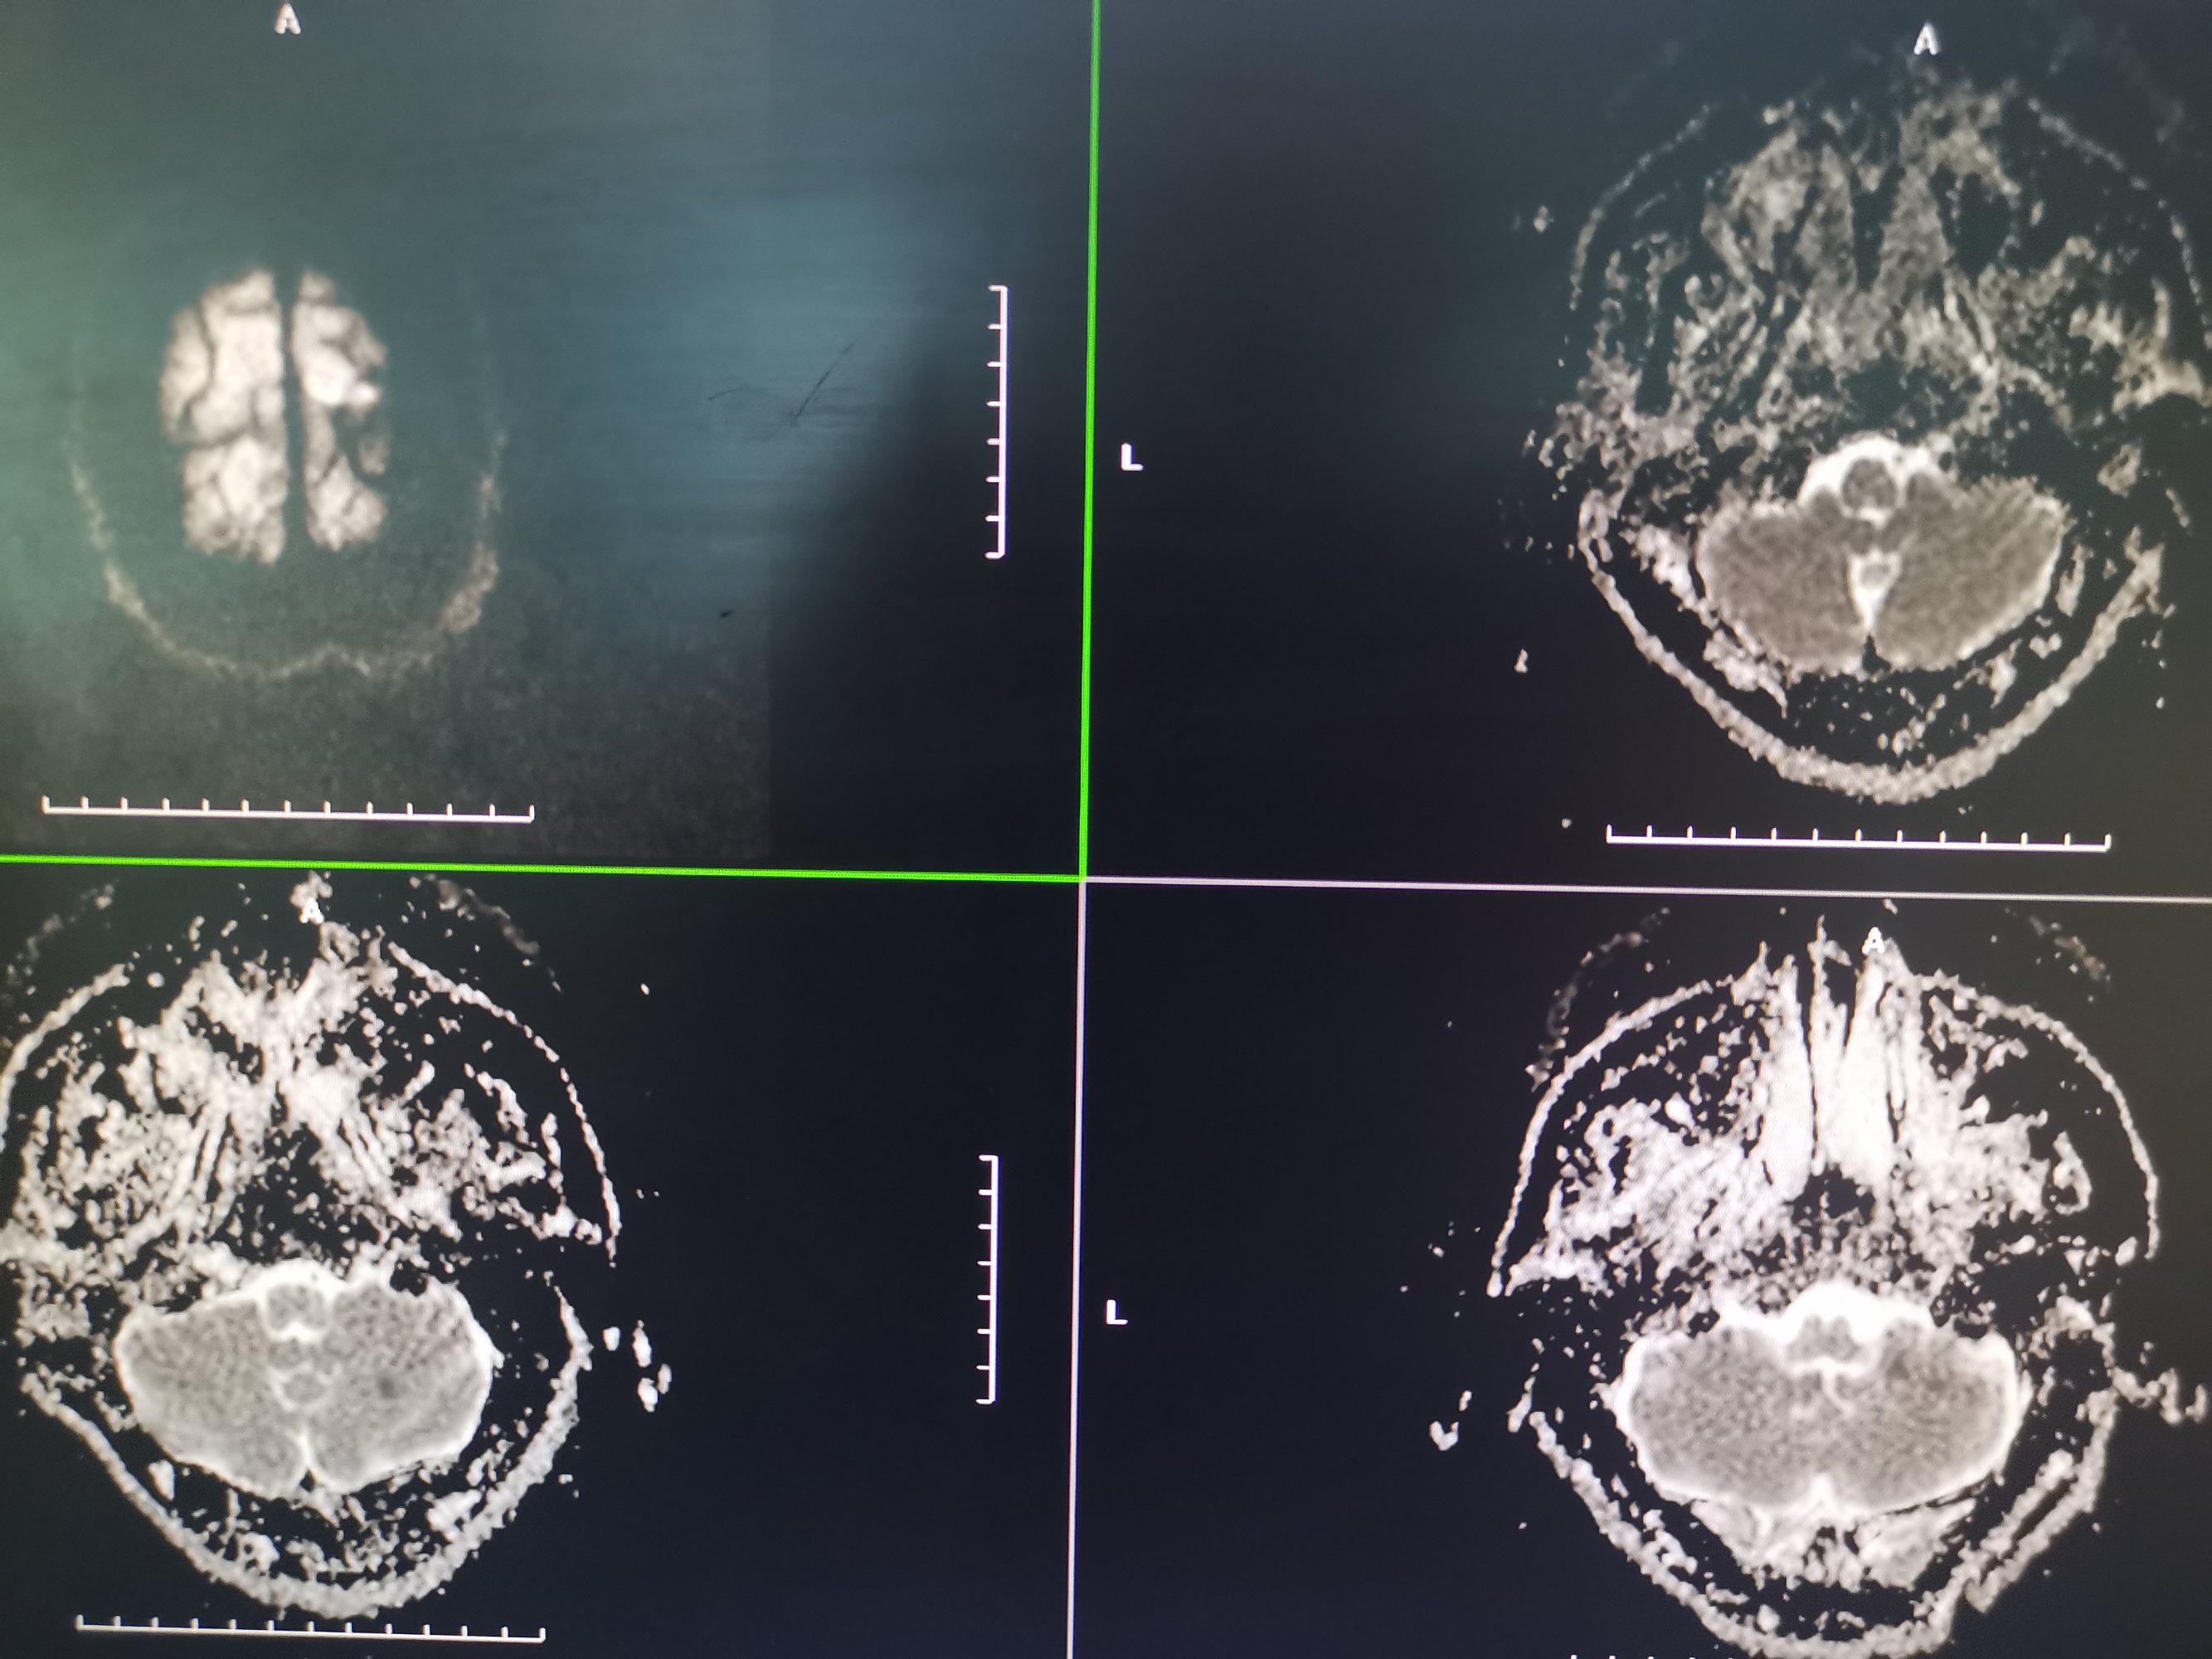

入院MR